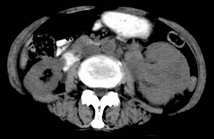

病患,女,69岁,左侧腰部不适,偶感疼痛2个月余,无化验室检查,行彩超发现左侧肾区实质性肿物,后行ct检查,结果同上。

左肾不规则软组织肿块,内见低密度坏死区,与正常肾实质分界不清,左肾明显增大,增强呈不规则条索状强化,肾盂及左输尿管上段扩张。肾周脂肪层受侵、模糊。印象:典型左肾癌。

平扫,表现为肾实质肿块,呈分叶状,肿块密度不均,内有不规则低密度区(陈旧性出血?坏死?)有的似呈囊性,增强明显不均一强化,与肾实质相比呈相对低密度的不均一肿块,肾周脂肪间隙可见,肾前筋膜未见增后,肾血管及腹主动脉旁未见肿大淋巴结影

左侧肾癌并肾静脉癌栓.腹膜后淋巴结肿大转移.

三期抓的不错,典型的肾癌,且已累及肾盂及左输尿管上段

左肾癌累及左输尿管,左肾静脉无受累征象。